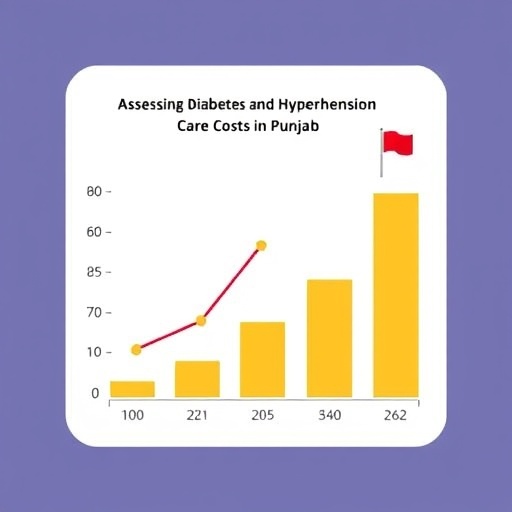

The research team meticulously aimed to quantify the costs incurred by primary and secondary-level government facilities in Punjab when delivering services for diabetes and hypertension. They employed a comprehensive methodology that encompassed both direct and indirect costs associated with patient management. This holistic approach enables a clearer understanding of the true financial burden faced by healthcare providers. By distinguishing between various types of costs, the study provides a nuanced view of economic pressures experienced at different healthcare tiers.

One particularly revealing aspect of the study is the analysis of direct costs, which include expenses for medications, medical supplies, laboratory tests, and personnel involved in patient management. The findings highlight that these direct costs account for a substantial portion of the total expenditure related to treating diabetes and hypertension. With the increasing incidence of these conditions, the financial demands on government facilities are expected to escalate, necessitating urgent attention from health administrators and policymakers.

A startling revelation from the study is the disparity in costs between primary and secondary-level government facilities. The results suggest that secondary-level facilities, tasked with more complex cases, bear disproportionately higher costs. This discrepancy underscores the necessity for integrating care at all levels of the health system to ensure that patients receive equitable treatment regardless of the healthcare facility they access. Moreover, it emphasizes the need for strengthening referral systems and enhancing the competence of primary-level facilities.